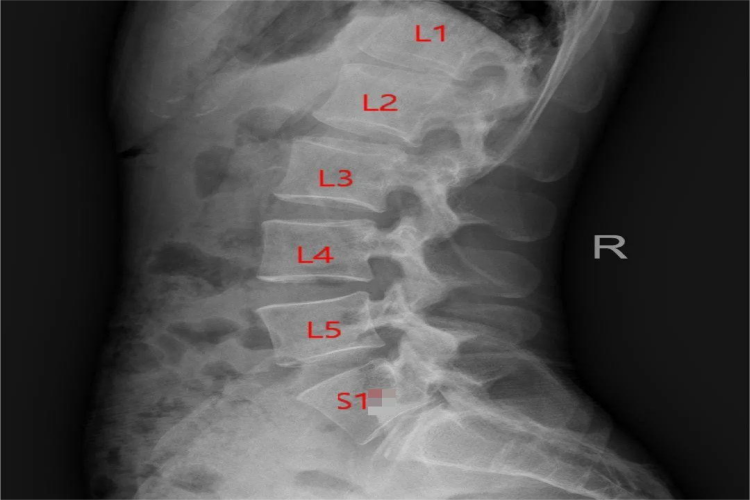

人的腰椎由5个互相分离的椎体构成,即L1-5,而骶椎的5个椎体则互相融合成为一块骶骨。骶椎腰化X线可观察到第一骶骨即S1游离出来形成第6个腰椎,长度增加,杠杆变长,下腰部的稳定性减弱,同时也使得骶髂关节的关节面的结构更加复杂,关节的稳定性受到影响,也容易造成损伤,导致腰痛。

椎骨的数目在胚胎发育过程中可出现变异,如第1骶椎不与其他骶椎融合,而形成第6腰椎,就会导致骶椎腰化的现象产生。